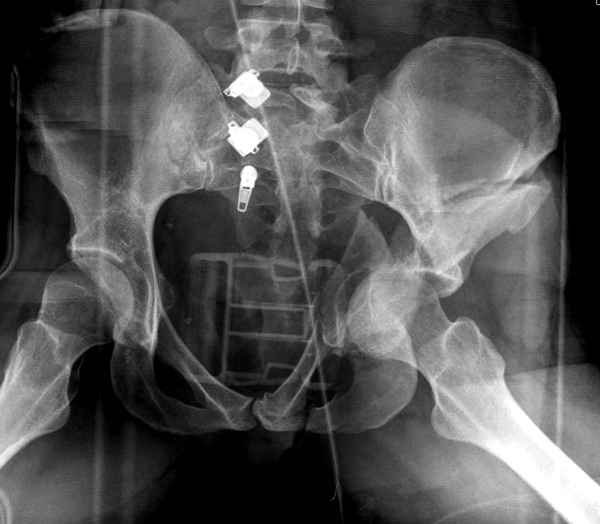

Все выступающие коллеги высказались насчет необходимости стандартных снимков по Judet, потому что для определения тактики лечения переломов вертлужной впадины 3Д снимки малоинформативны.

Летурнель разработал классификсацию на основании прямого, запирательного и подвздошного рентген снимков, котоые, кроме описания характера переломов, также подсказывают адекватный доступ для репозиции перелома.

Из того минимума, что представлено, мне кажется, мы имеем дело с двухколонным переломом вертлужной впадины. Обычно медиальный (центральный) "вывих" головки встречаются в сложных двухколонных переломах со смещением.

Здесь несколько вариантов двухколонных свежих переломов, которые были оперированы из одного-заднего, а также из двух: переднего и заднего доступов.